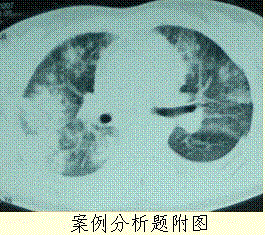

问题 患者女,23岁。间断发热伴皮疹1年半,诊断红斑狼疮。长期间断应用糖皮质激素治疗。近20 d高热(T 39℃)伴咳嗽咳痰, CT(附图)示双肺满布圆形密度增高阴影,大小不等,密度不均匀,上、中肺野分布较多,双侧少量胸腔积液。血常规:WBC 2.52×10/L, N 0.62, Hb 92 g/L;ESR 40 mm/h;痰真菌培养:烟曲霉3次阳性;支气管镜检查右下叶、左舌段见黄色黏液性血性分泌物,毛刷找到霉菌孢子。 本例肺部病变性质诊断可能为

选项 A.红斑狼疮的肺部并发症 B.合并大叶性肺炎 C.合并 ARDS D.合并肺真菌感染 E.肺部转移瘤

答案 D